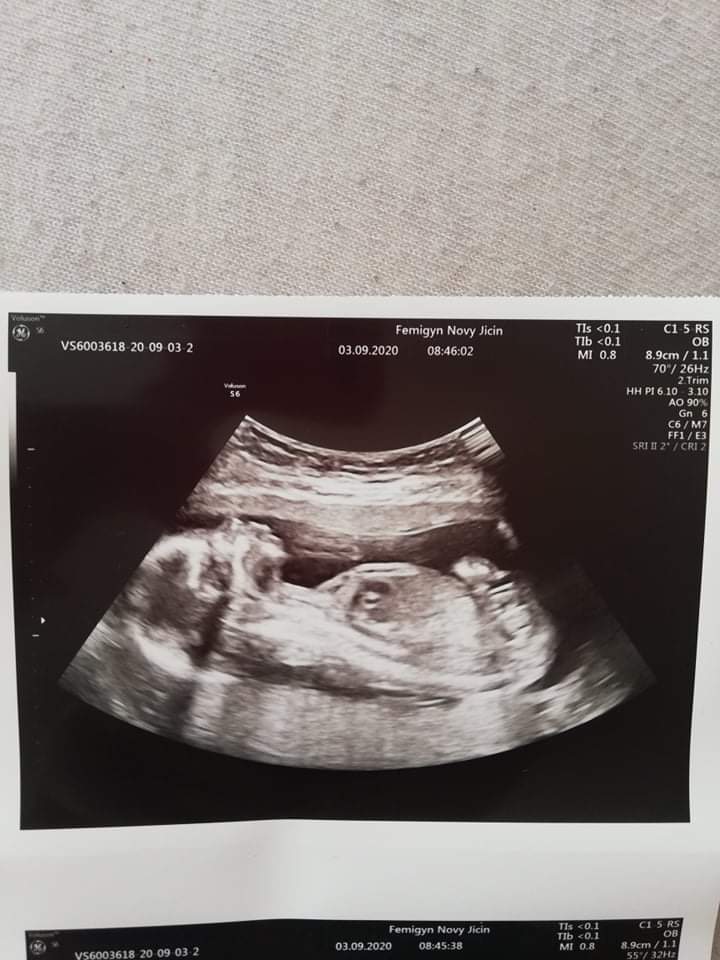

Ahoj maminky a budoucí maminky 😉 Prosím, poradila byste mi některá, co vidíte na fotce z ultrazvuku ve 20. týdnu za pohlaví? Určitě jste foteček viděly už mraky, proto vás žádám o radu...Nechci nikoho ovlivnit, proto svůj tip řeknu později 🙂 Děkuju moc!!!

@miiiissssanek cca 18. týden

@pavlinkadv na této fotce nevidím pohlavní hrbolek, jiné foto?

@pavlinkadv No jenže v tom 17. týdnu už není pohlavní hrbolek, ten je kolem 13. týdne

Ze 17. tt dávala jiná nastávající maminka 😊

@pavlinkadv Aha, no i tak to jde špatně vidět, ale u Vás bych řekla spíše chlapeček, zdá se mi, že se tam něco stohuje nahoru 😉